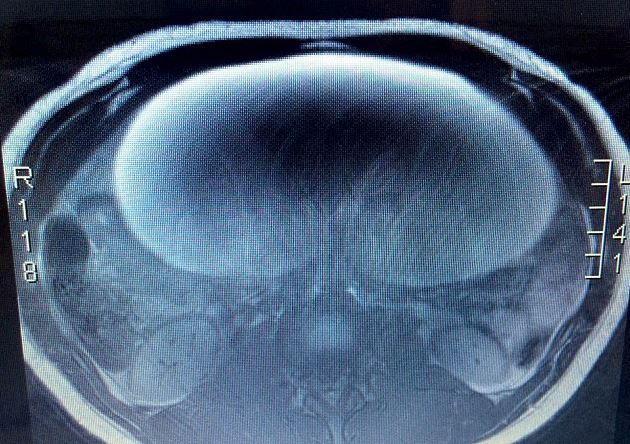

Όταν οι γιατροί είδαν την αξονική της, ανακάλυψαν ότι η κύστη της Olivia είχε φτάσει το μέγεθος ενός καρπουζιού.

Ενώ ο ίδιος ο όγκος δεν ήταν μεγάλος, οι διαστάσεις της κύστης ήταν απίστευτες.

Ευτυχώς, μετά την αφαίρεση του όγκου και της κύστης, μήκους 30 εκατοστών, οι γιατροί ανακοίνωσαν στην Olivia ότι ο καρκίνος δεν είχε εξαπλωθεί.